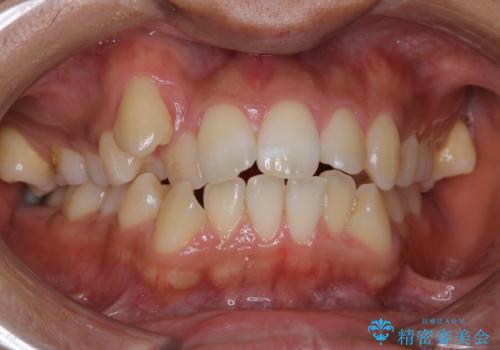

ハーフリンガル ワイヤー矯正による非抜歯・過蓋咬合の治療

- 20代女性

- 非抜歯、大臼歯遠心移動による臼歯関係の是正・過蓋の改善をハーフリンガル・ワイヤー矯正にて計画した。

現在過蓋咬合の非抜歯治療はマウスピースで行うのが第1選択といっても過言ではありません。

しかし、諸々の理由でマウスピース矯正をおこなえない場合、本例のようにワイヤーを用いて治療することも可能ですが、そもそも装置が歯につかないため、非常に大変な労力を費やすことになります。